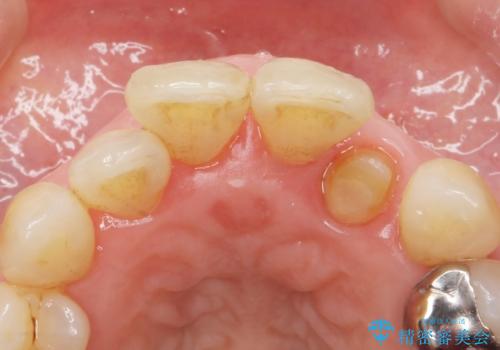

入れ歯も抵抗があるとのことから、相談を重ね、今の状態では保存不可能な下の前歯(左下2)を抜去し、ブリッジや連結補綴により動揺を抑えることにしました。

また、咬み合わせが反対になっている上の前歯(左上2)も補綴で形を変えることにより、咬合を改善しました。

下顎大臼歯が欠損したままで今ある歯に負担がかかりやすいことから、長期的予後は保証できないことをご理解頂いた上で治療を行いました。